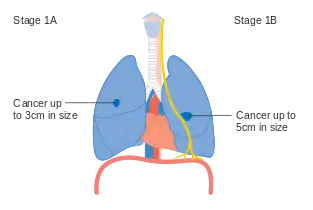

Lung cancer staging is an assessment of the degree of spread of the cancer from its original source.[77] It is one of the factors affecting both the prognosis and the potential treatment of lung cancer.[2][77]

The evaluation of non-small-cell lung carcinoma (NSCLC) staging uses the TNM classification (tumor, node, metastasis). This is based on the size of the primary tumor, lymph node involvement, and distant metastasis.[2]

Using the TNM descriptors, a group is assigned, ranging from occult cancer, through stages 0, IA (one-A), IB, IIA, IIB, IIIA, IIIB, and IV (four). This stage group assists with the choice of treatment and estimation of prognosis.[80]

- Diagrams of main features of staging

- Stage IA and IB lung cancer

- Stage IIA lung cancer

- Stage IIB lung cancer

- One option for stage IIB lung cancer, with T2b; but if tumor is within 2 cm of the carina, this is stage 3

- Stage IIIA lung cancer

- Stage IIIA lung cancer, if there is one feature from the list on each side

- Stage IIIB lung cancer

- Stage IV lung cancer